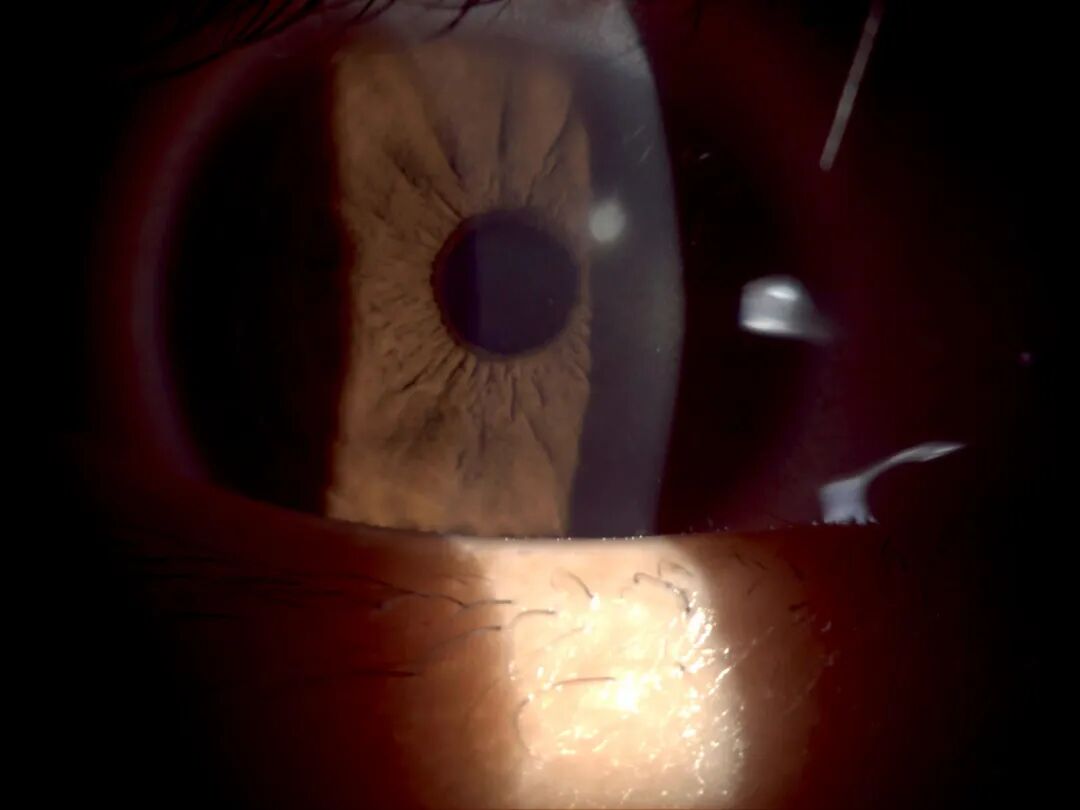

角膜缘分光照明法

利用角膜透明性,使光线在角膜组织内形成全反射。

裂隙灯上光源是什么裂隙灯显微镜常用检查方法_https://www.jmylbn.com_新闻资讯_第12张

棘阿米巴角膜炎:环形角膜浸润

操作要点

• 光源亮度:最强亮光

• 裂隙宽度:3~5mm,中等裂隙

• 裂隙高度:10mm,角膜上有光照,巩膜上没有

• 裂隙夹角:45°~60°

• 放大倍率:10x或16x

• 先将裂隙光聚焦在角膜缘,松动离焦旋钮,照明光线离焦,光带调亮调宽,显微镜焦点聚于角膜处进行观察,此时角膜缘呈现光晕及一环形阴影。正常的角膜本身将无所见

• 观察:角膜上细微、范围较大病灶,如角膜云翳、水泡、水肿、棘阿米巴角膜炎:环形角膜浸润